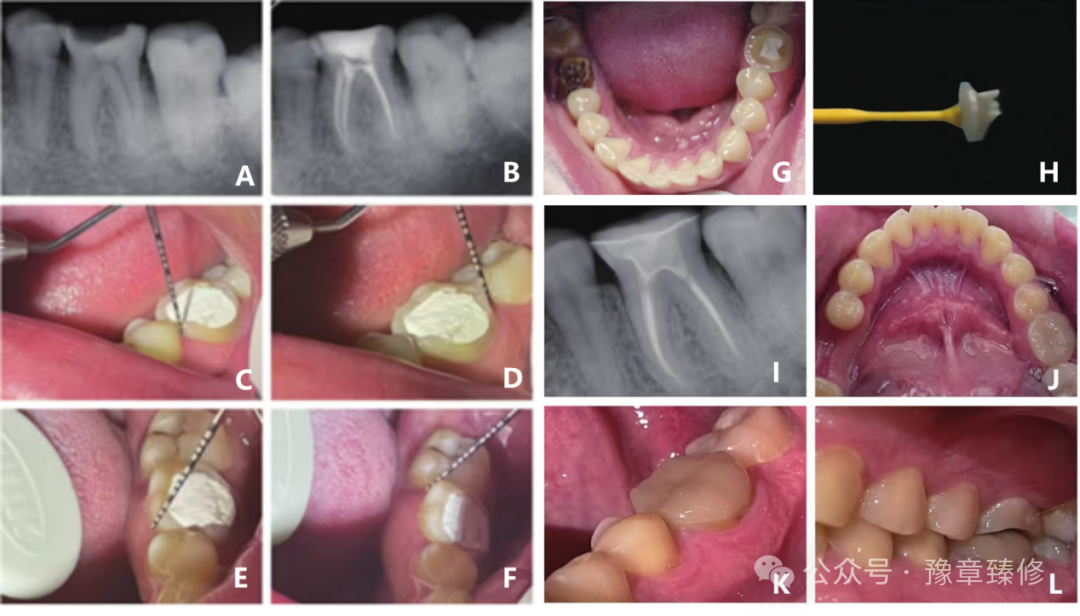

与传统铣削需要去除额外材料保证刀具进入修复体尖锐边缘处不同,3D打印氧化锆无需进行刀具补偿,可以获得更紧密的边缘贴合(图7)(临床可接受边缘间隙<120μm[19],NPJ冠平均间隙仅约63.9μm[18],显著优于铣削冠)。这种优异的边缘精度,结合其高编程分辨率(16,000×17,625μm)与超薄层打印(10.5μm层厚[18])技术, 可以获得更高的整体和外部尺寸精度[18](图8),尤其在精细复制沟窝等复杂解剖结构方面表现出一定优势(图9)。高精度与高密合度为短冠基牙与修复体之间的摩擦力提供了保障,从而提高固位力。

图11:不同肩台形态制作的牙冠边缘在 3D 激光扫描显微镜下的观察光固化成型(SLA)组:(A、B、C)圆钝线角边缘显示轮廓光滑,无微小瑕疵;(D)存在较大崩瓷。铣削组:(E、F)尖锐线角边缘可见分散的崩瓷;(G、H)刃状肩台牙冠中观察到更多且更大的崩瓷。(箭头:轮廓线;星号:瑕疵与崩瓷)